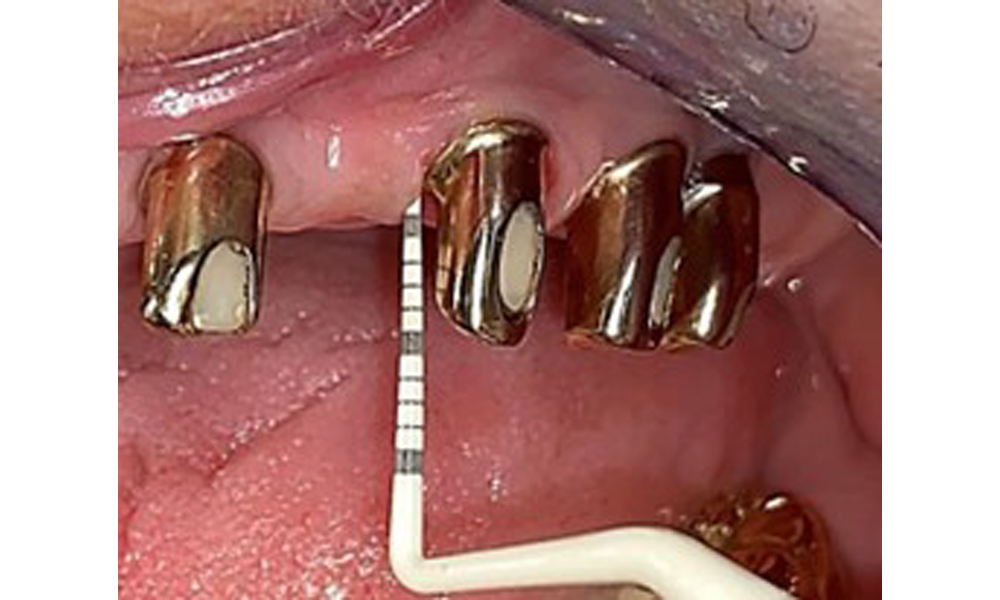

The dental findings are as follows: Combined removable implant and tooth-supported telescopic prostheses on implants 15, 13, 21, 23, 24, 25 and tooth 11 (Fig. 1, Fig. 2, Fig. 3). The patient was fitted with a fixed mandibular denture. Adequate bridges were present over 37 to 34 and 45 to 47 (Fig. 4), the crown margins were intact and there were no active caries. A composite filling with a marginal gap was present on tooth 43. There was mandibular gingival recession, exposing 1 to 3 mm of root surface. This also applies to 11.

Occlusal view of the mandible.

Fig. 4: Occlusal view of the mandible.